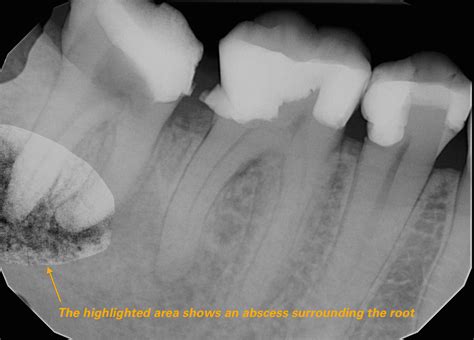

A root abscess, clinically known as a periapical abscess, is a painful condition that requires immediate dental attention. Many people search for root abscess pictures online to understand what this condition looks like, often because they are experiencing discomfort and are worried about the state of their oral health. Understanding the symptoms, causes, and visual indicators of a dental abscess is crucial for recognizing when a minor toothache has escalated into a serious infection that needs professional treatment.

A root abscess is a localized collection of pus caused by a bacterial infection at the root of a tooth. This infection typically occurs when bacteria enter the tooth through deep cavities, fractures, or failed dental work, reaching the pulp—the inner part of the tooth that contains blood vessels and nerves. As the body attempts to fight this infection, it sends white blood cells to the area, resulting in the formation of pus. If this pus cannot drain, it forms an abscess, leading to intense pain and potentially serious complications.

When searching for root abscess pictures, you will often notice a common visual sign: a small, pimple-like bump on the gums near the affected tooth, known as a fistula. While not all abscesses present this way, it is a hallmark sign that the body is trying to drain the infection.

Professional dental intervention is the only way to treat a root abscess effectively. A dentist will typically perform an X-ray to confirm the diagnosis and determine the extent of the infection. Treatment options generally include: